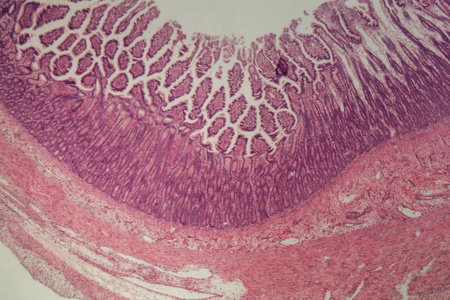

这个是显微镜下的小肠切片.

小肠绒毛,光镜下

横截面小肠

显微镜下小肠c.s.